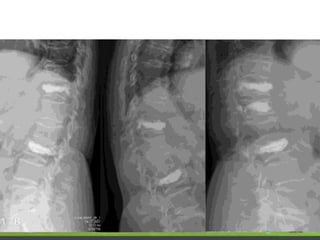

因骨鬆疾病造成壓迫性骨折,行動不便,長期臥床 ,導致褥瘡,反覆呼吸道/泌尿道感染住院治療,耗 費高昂的醫療成本、家屬及社會經濟的沉重負 擔。

台灣邁入老年化社會  骨鬆合併壓迫性 骨折發生率急速增加

骨鬆合併壓迫性骨折發生率急速增加

只有約25%的脊椎骨 鬆骨折會有臨床症狀

脊椎骨折常被忽略 !!